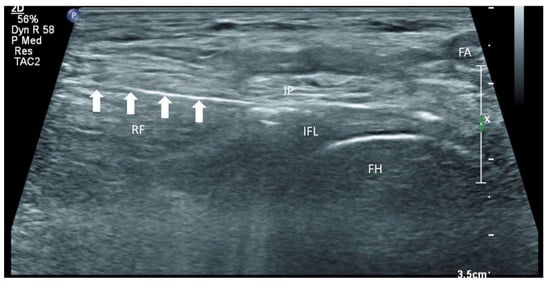

Figure 1. Nerves supplying the hip joint and their relationship to the femoral vessels. Reproduced with permission from Dr Maria Fernanda Rojas Gomez (Bucaramanga, Colombia).

The growing impact of fragility hip fracture on the healthcare system and on society has become a major concern worldwide. Despite the advances in perioperative medicine and anaesthetic care, a minority of frail patients are still too ill to be surgical candidates. Hip fracture analgesia generally includes non-pharmacological modalities, oral and injectable analgesics, traction and regional nerve block [1,2]. However, given the complexity of medical comorbidities in this patient population, pain management of hip fracture is not a one-size-fits-all recipe [1]. Acupuncture, relaxation therapy, and transcutaneous electrical nerve stimulation (TENS) may be associated with potentially clinically meaningful benefits, but no firm conclusion can be drawn from the current evidence [1]. Comorbidities may also prohibit the use of these therapies, for instance, pacemakers and anticoagulants. Simple non-opioid analgesics are often insufficient to treat dynamic pain adequately, whereas opioid analgesics can cause disturbing side effects in this patient population, such as dizziness, nausea and vomiting, sedation and even respiratory depression. Traction does not reduce the intensity of acute pain, and patients also remain bed-ridden during this treatment [2]. Regional nerve blocks, such as Pericapsular Nerve Group (PENG) block, fascia iliaca block and femoral nerve block, can effectively manage fracture pain, especially if a catheter is inserted [1,2,3]. Nevertheless, the benefit from a single shot regional nerve block can usually last for 1 to 3 days whilst there is an infective concern if a block catheter is placed for weeks. Community management of the catheter is also a practical concern in our locality. Partial hip denervation hence becomes a treatment option to provide long-lasting analgesia by a single intervention. With the sophistication of ultrasound technology coupled with a greater understanding of hip joint innervations in recent cadaveric studies (Figure 1), there has since been a venture to develop an ultrasound-guided approach to denervate the hip joint. The first such approach was described by Sasaki et al. in 2018 [4], where alcohol was infiltrated superficially over the ligaments encasing the anterior hip joint, namely the iliofemoral and pubofemoral ligaments. Subsequent to our case series demonstrating the efficacy of the conventional approach, which consisted of a PENG injection and an oblique approach to the obturator nerve articular branches (ONAB) [5], we noticed there were circumstances in which the conventional approach did not work well, and enormous technical difficulties were encountered in terms of needle trajectory.